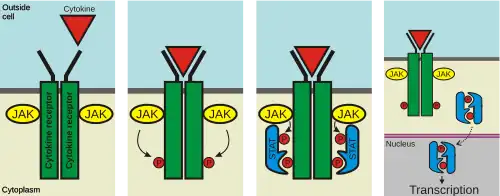

Cytokine receptor

Cytokine receptors are receptors that bind to cytokines.[1] The binding of cytokines to receptors allows the cell that houses the receptor to be able to receive the signals of another cell. These receptors can be found on the surface of cells that allows them to communicate with other cells that transmit their signals [2]This interaction between cells can involve genetic output, cell cycle changes and other signal transduction responses. Cytokine Receptors play a crucial role in Immunological response.

| type I cytokine receptor | Certain conserved motifs in their extracellular amino-acid domain. Connected to Janus kinase (JAK) family of tyrosine kinases. Many have a FN-III superfamily domain and an immunoglobulin-like fold. | JAK phosphorylate and activate downstream proteins involved in their signal transduction pathways | |